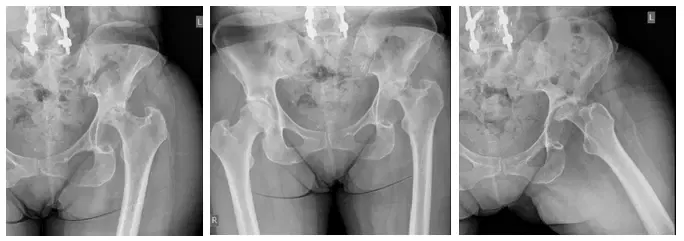

La señora M. es una mujer de 49 años que creció en Irán y se trasladó a Canadá hace varios años. Sufría molestias leves en la cadera desde hacía muchos años y se había sometido a una intervención en la cadera izquierda en su Irán natal, cuya naturaleza se desconocía....

El paciente es un varón de 55 años que acudió quejándose de dolor bilateral en la cadera que, según declaró, había ido en aumento durante los últimos meses. El paciente acudió con radiografías para revisar, que indicaban que tenía artritis bilateral de las...

El paciente es un varón de 68 años que acudió en 2010 remitido por otro traumatólogo. El paciente se quejaba de dolor en la cadera izquierda que, según declaró, le venía molestando desde hacía dos años. El paciente había mencionado que fue hospitalizado hace un año...

La paciente es una mujer de 55 años que acudió con fuertes dolores. La paciente explicó que hace tres años tuvo una fractura intertrocantérica de la cadera izquierda y una fijación interna de reducción abierta (ORIF) realizada por una institución externa. Afirmó que...

La paciente es una mujer de 75 años que acudió a nosotros con dolor intenso en la cadera izquierda tras someterse a una fijación interna de reducción abierta (ORIF) de la cadera izquierda. El paciente vino con radiografías para revisar, como se muestra a continuación,...